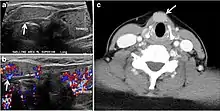

Fig. 16. Midline ectopic thyroid with Hashimoto's thyroiditis in a 49-year-old female patient. a Transverse greyscale ultrasound shows a 1.6 × 0.8 cm solid, well-defined, heterogeneous area (white arrow) in the midline, superior to the thyroid gland. It is iso-echogenic to the thyroid gland with no definite connection to the thyroid gland. b Transverse colour Doppler ultrasound shows significant increase in vascularity. c Axial enhanced neck CT scan at the level of thyroid cartilage demonstrates midline infrahyoid hyperdense soft tissue mass (white arrow) embedded within the strap muscle.[1]